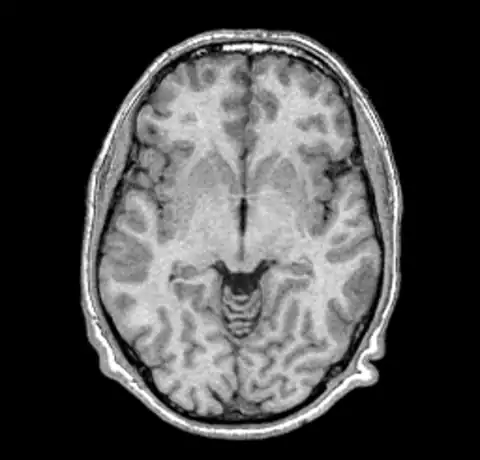

We can now take a look at the corrected file (out.mnc)

As it is very hard to pick the differences between the original and corrected version we can create a field image to visualise the differences.

And then for completeness sake, here are the original and corrected image using a spectral colormap to better visualise the change. Note that in the second (corrected) image the intensity of the white matter is more uniform (the red part).